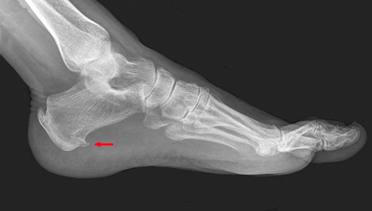

▶影像学检查可确诊,包括X光检查、超声和核磁共振。

图5:X光片示跟骨结节可见骨刺(红色箭头)